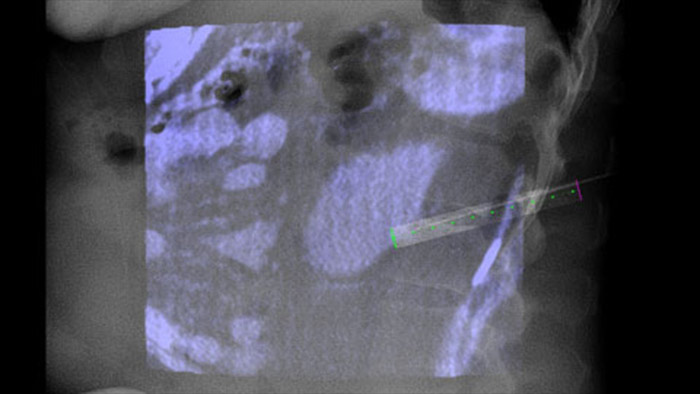

XperGuide provides highly accurate live image guidance of each needle to a targeted position by overlaying pre-planned trajectories with fluoroscopic imaging.3

Lesion heterogeneity and lack of conspicuity limit the quality of specimens as well as the feasibility of biopsies when performed under ultrasound or conventional CT. With the increasing adoption of screening programs in lung, early lung cancers manifesting as small nodules have been detected more frequently than ever before. 14.5% of a screened population was observed to have nodules ≤10 mm.1-2 Our needle navigation technology with CBCT increases precision, and enables the targeting of smaller (<=1 cm) or heterogeneous lesions more accurately with less needle repositioning and at lower dose than conventional CT.1-2